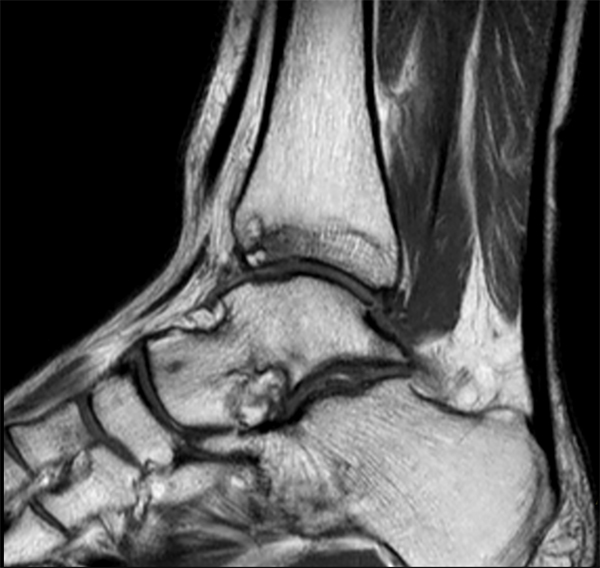

Sagittal PDW TSE